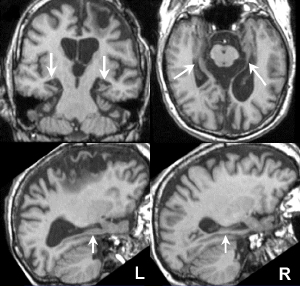

И вот теперь в руки канадских психологов попали сразу два уникальных пациента, у которых в результате черепно-мозговой травмы произошли психические изменения еще более редкого и избирательного свойства. Оба мужчины (K.C. и M.L.) стали объектами пристального внимания ученых из-за дорожной аварии (один был мотоциклистом, другой велосипедистом). У обоих от сильного удара головой полностью отшибло эпизодическую память. При этом большинство других психических функций осталось в пределах нормы. Пациенты сохранили нормальный уровень интеллекта (IQ = 102 и 108). При них остались все те знания, которые они успели получить до травмы (то есть семантическая память не пострадала). Правда, способность приобретать новые знания они в значительной степени утратили из-за повреждений гиппокампа и других отделов мозга. Но все личные воспоминания стерлись напрочь. Пациенты не могут вспомнить ни одного эпизода из своей жизни — ни до травмы, ни после.